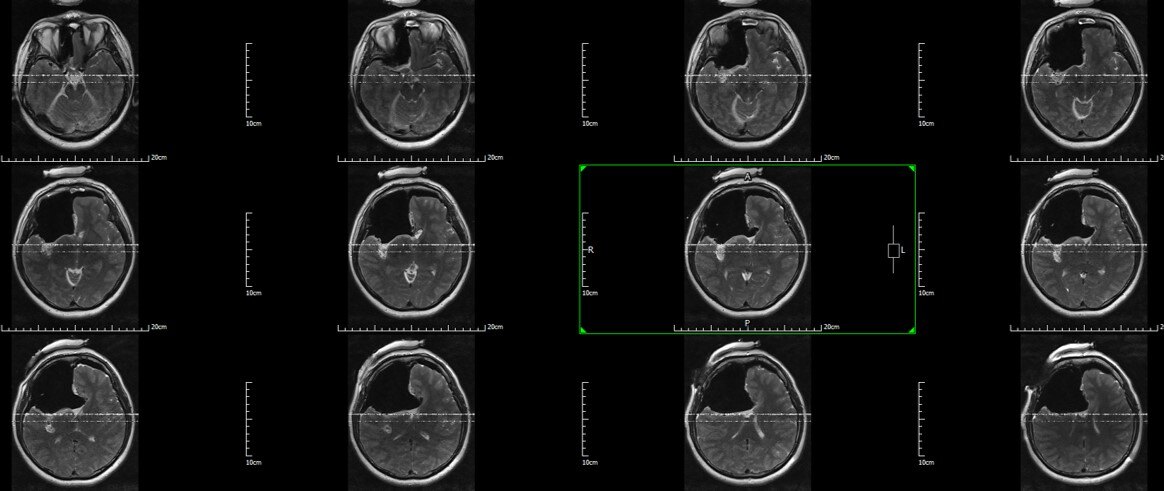

不幸的是,2年后迅速复发,再次手术(此次)。肿瘤出现强化,肿瘤通过胼胝体向左额进展,右侧岛叶也信号异常,膨胀性改变。术前诊断:右额-胼胝体-岛叶胶质瘤

术前增强T1

术前T2 Flair:右额-胼胝体-岛叶胶质瘤

术前T2